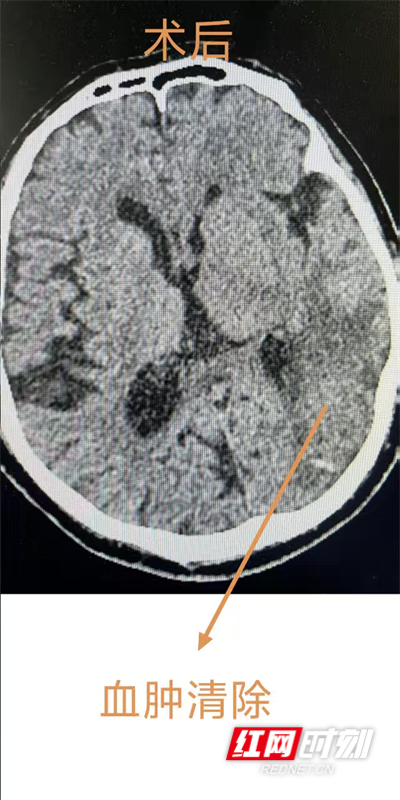

神经外科等科室医生迅速参与会诊,结合患者心脏支架植入后的身体状况,评估认为当前外科手术风险极高,团队一致决定暂时采取保守治疗,将患者转入NICU进行24小时严密监护。由于患者接受了心脏支架手术,需服用抗凝药物防止支架内血栓形成,而抗凝药物又可能导致脑出血继续增加,手术后新发出血可能性很高,主动耐心细致地与患者家属沟通病情及治疗方案,打消他们的顾虑。4天后患者左侧脑内出血量明显增加,可能危及生命,随即启动多学科协作讨论,联合心血管内科、ICU、麻醉科评估手术风险及耐受性,决定采用颅骨钻孔血肿碎吸引流术这一微创术式,精准定位、颅骨钻孔、血肿腔穿刺引流,短短数十分钟,手术取得圆满成功。

术后,患者返回ICU接受高级生命支持,病情得到有效控制,患者神志与肌力逐渐改善,转入神经外科普通病房。护理团队贯彻早期康复理念,术后第三天即开始良肢位摆放、关节被动活动等基础护理,并指导家属参与肢体按摩与被动训练,针对患者可能出现的运动与吞咽障碍,团队制定分阶段个性化训练计划,全程跟进、动态调整。